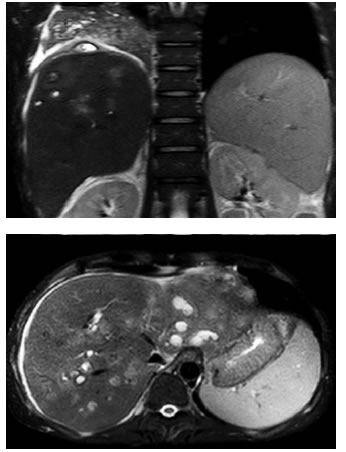

En la resonancia magnética (RM) de abdomen, con contraste (Primovist®, gadoxetato disódico, Bayer), se evidenciaron múltiples abscesos, uno de ellos con compromiso extrahepático subdiafragmático y en íntima relación con el lóbulo pulmonar inferior derecho. Además, se observó obstrucción segmentaria del árbol biliar, derecho e izquierdo, con engrosamiento concéntrico de las paredes, realce tardío y sin evidencia de masa, cambios que sugerían un proceso inflamatorio antes que una lesión neoplásica (figura 3).